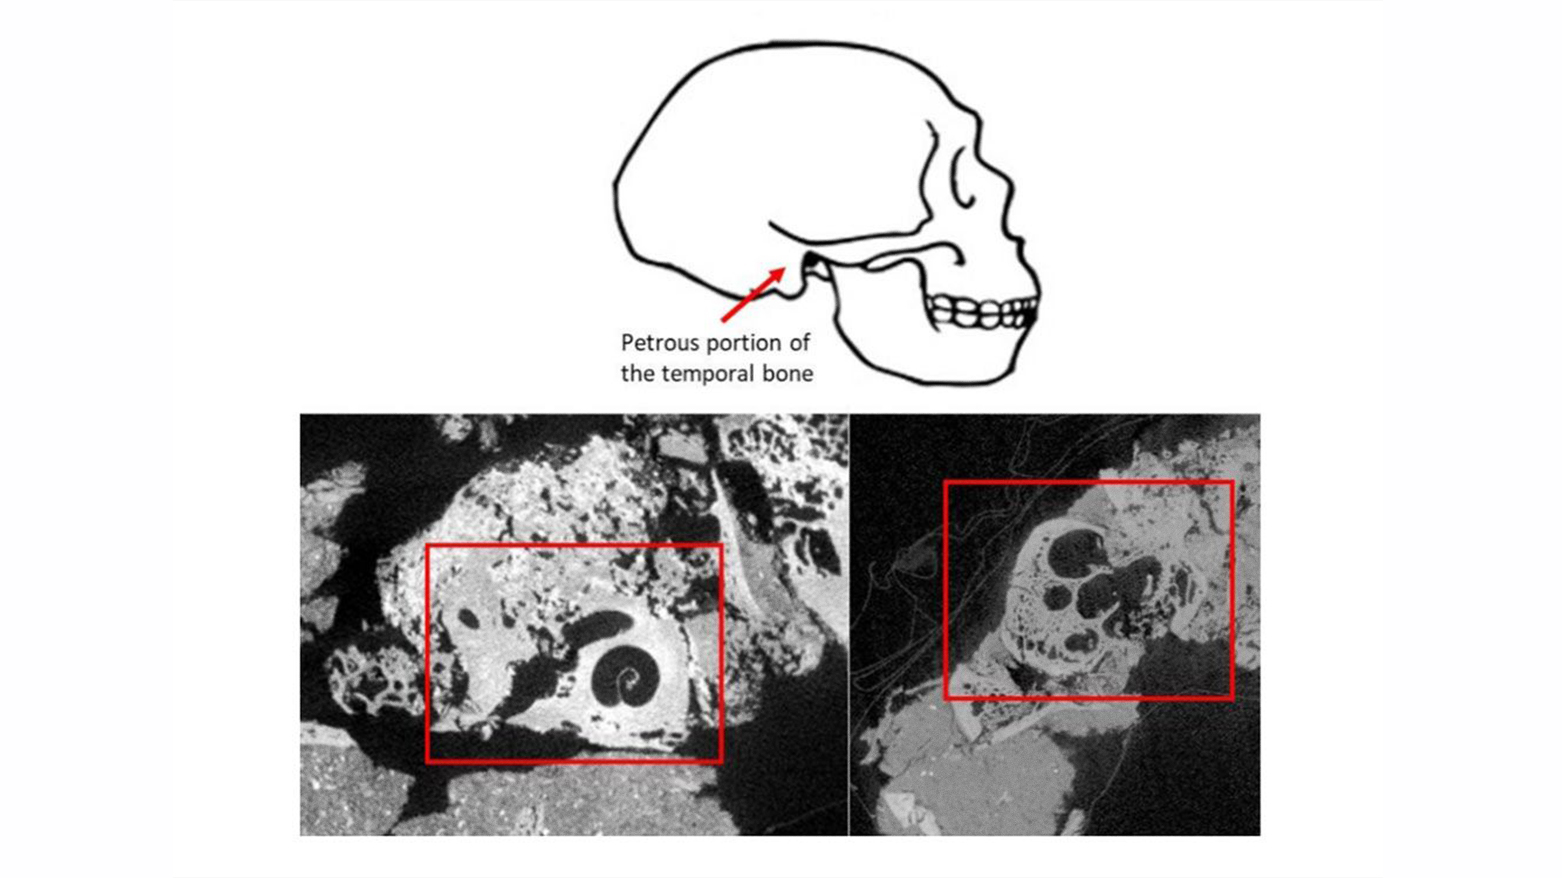

بەپێی ئاماری پەیمانگای شوێنەواری ئەمریکا، زاناکان بە وردی کاسەسەری پارچەپارچەکراوی شانەدەر Zیان بە بەکارهێنانی ڕێگەی پێشکەوتووی وەک شیکاریی پڕۆتینی مینای ددان و سی تی سکان دروست کردووەتەوە.

لە ڕێگەی تەکنیکە داهێنەرەکانی وەک شیکاری پڕۆتینی مینای ددان و سی تی سکان، توێژەران توانیان بە وردییەکی بێوێنە دەموچاوی ئەم نیاندەرتاڵە دروست بکەنەوە. مۆدێلەکە کە لەلایەن شوێنەوارناسانی کۆن ئادری و ئەلفۆنس کێنیسەوە دروست کراوە، وێنایەکی سەرنجڕاکێشی ئافرەتێکی نیاندەرتاڵ پێشکەش دەکات کە نزیکەی 75 هەزار ساڵ لەمەوبەر ژیاوە.